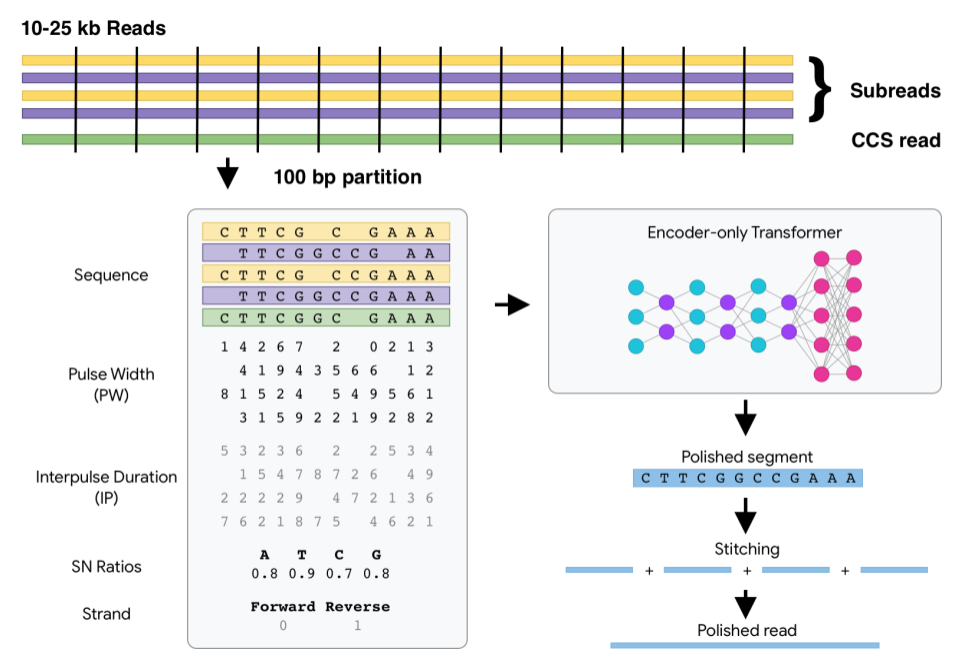

以基因组学领域为例。计算机从一开始就对基因组学很重要,但是机器学习增加了新的功能并颠覆了旧的模式。当谷歌的研究人员探索这一领域的工作时,许多专家认为利用深度学习来推断基因变异的想法是牵强的。如今,这种机器方法被认为是最先进的。谷歌发布的开源软件 DeepConsensus 以及与加州大学洛杉矶分校(UCSC)合作的 Pepper-DeepVariant 提供了尖端的信息学支持。我们希望更多的快速测序可以在近期进入实际应用领域,并对患者产生实际影响。

以基因组学领域为例。计算技术一直对基因组学非常重要,但机器学习方法改变了之前的旧模式,并增添了新的功能。最初,谷歌的研究人员使用机器学习在该领域展开研究时,许多专家认为使用深度学习技术从测序仪中推断是否存在基因变异的想法是不可行的。但如今,机器学习是最先进的研究方法。并且未来机器学习将扮演更重要的角色,比如基因组学公司正在开发更精确、更快的新测序仪,它需要匹配更好的推理能力。我们也发布了 DeepConsensus 开源软件,以及与 UCSC 合作的 PEPPER-DeepVariant,为这些新仪器提供最前沿的信息学支持。我们希望这些性能更强的测序仪可以尽快应用在实际患者中并产生有益影响。

图丨DeepConsensus 中的 Transformer 结构示意图,它可以纠正测序错误,提高准确率。

图丨DeepConsensus 中的 Transformer 结构示意图,它可以纠正测序错误,提高准确率。